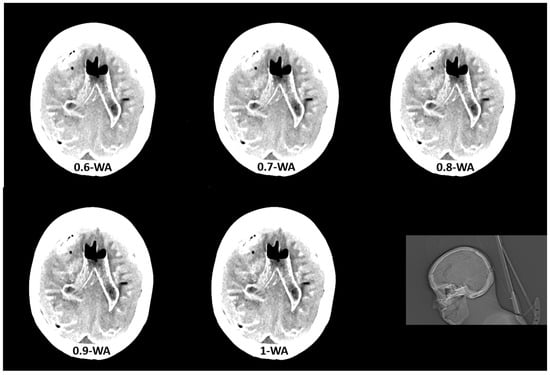

GM–WM CNR and noise generally increased when WF values increased from 0 to 1 (Figure 6). The 0.9-WA reconstructions had the highest CNR, and 0-WA and 0.1-WA had the lowest. SCA and PFAI were lowest for 0-WA images and highest for 1-WA images. Qualitative analysis showed unacceptable GM–WM contrast on 0-WA, 0.1-WA, and 0.2-WA image datasets for two readers. All readers rated GM–WM contrast as very good or excellent at 0.5-WA, 0.6-WA, and 0.7-WA. No or minimal posterior fossa and subcalvarial artifacts were noted at 0-WA, 0.1-WA, 0.2-WA, 0.3-WA, and 0.4-WA, while 0.9-WA and 1-WA reconstructions were considered unacceptable or for very limited evaluation by all readers. The overall IQ was rated as very good or excellent by at least two readers for the 0.5-WA, 0.6-WA, 0.7-WA, and 0.8-WA image datasets. The interrater consistency results for the assessment of the different IQ metrics for all 11 image datasets are presented in Table 2. The agreement for SCA assessment was moderate, while the interrater agreement for noise, GM–WM contrast, PFA, and overall IQ was good.

Figure 6.

Box and whisker plot of the contrast to noise ratio (CNR) with different weighting factor (WF) in the phantom.

As expected, GM–WM CNR was highest at high WFs, while the reconstructions with the lowest WFs exhibited minimal artifacts in the phantom scans. As anticipated, noise metrics such as SCA and PFAI decreased with lower WFs due to greater contribution of 140 kVp acquisition data to the final WA reconstructions, resulting in higher maximum X-ray beam energy and, consequently, less noise and fewer artifacts. Conversely, GM–WM CNR increased with higher WFs and a greater proportion of low-energy data in the final WA images. However, the WA reconstructions with the highest measured and subjectively perceived GM–WM CNR (WF 1 and 0.9) and those with minimal or no artifacts (WF 0, 0.1, 0.2, and 0.3) were rated overall by readers as non-diagnostic and, thus, clinically useless. The readers found that WA reconstructions with WFs of 0.5, 0.6, 0.7, and 0.8 had the best overall IQ, which indicates that the optimal balance between GM–WM contrast and artifacts is achieved at these mixed energy ratios.